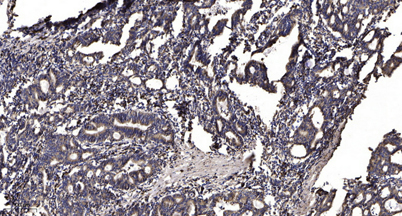

| Dilutions: | WB 1:500-2000;IHC-p 1:50-300; ELISA 2000-20000 |